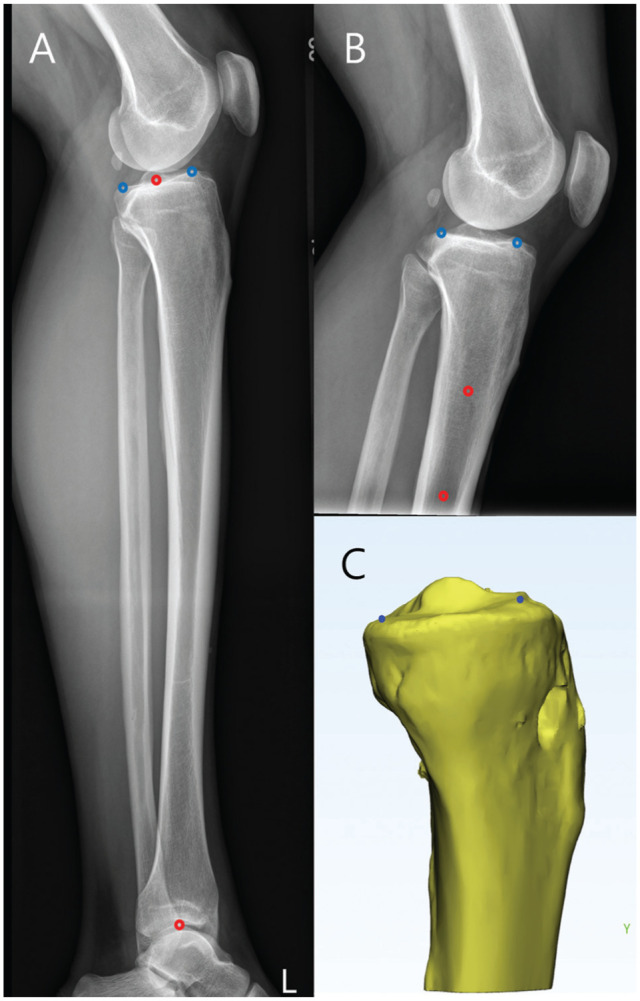

Purpose/hypothesis: The purpose of this article was to evaluate the accuracy of calculating the lateral plateau slope using lateral radiograph (LR) and magnetic resonance imaging (MRI)-derived asymmetry. It was hypothesized that measurement error would be high and variable across imaging modalities and that 3-dimensional (3D) reconstruction would serve as a consistent and accurate reference for PTS assessment.

Methods: Between March 2020 and October 2023, ACL reconstruction patients were screened. PTS was measured on knee LRs, tibial long-bone LRs (LLRs), preoperative MRI, and 3D-reconstructed images from postoperative computed tomography scans. Two orthopaedic surgeons performed 2 measurements each. Reliability was assessed using intraclass correlation coefficients (ICCs), and agreement was analyzed using Bland-Altman plots, considering ±2° limits of agreement (LOA) as acceptable.